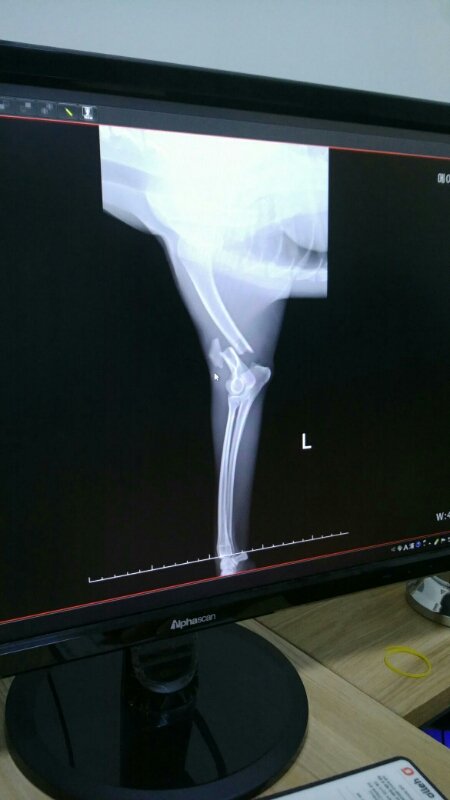

24시병원으로 옮겨 검진결과

앞두다리 골절과 골반 양쪽골절.

심장비대 신장기능이 멈춰 몸에 독소가 가득하답니다.

2~3일 지켜본후 수술여부를 결정한다고 하십니다.